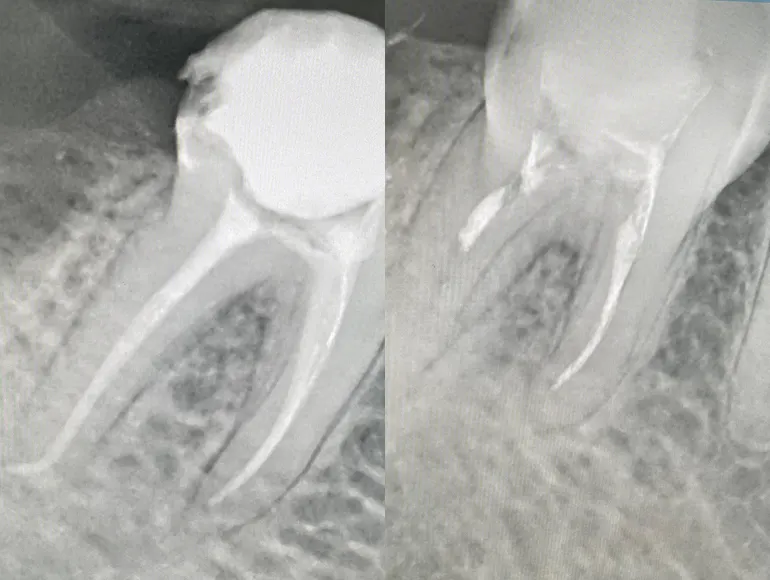

Teeth With Unconventional Number of Roots or Canals

Case by Dr. Taha Azimaie: Identifying unconventional number of roots and canals is the key in long term survival of the tooth. Tooth number 4, upper right premolar, usually have 1 pulp chamber, 1 root and 1 canal. This tooth have complex shape with 2 pulp chambers and 3 canal.